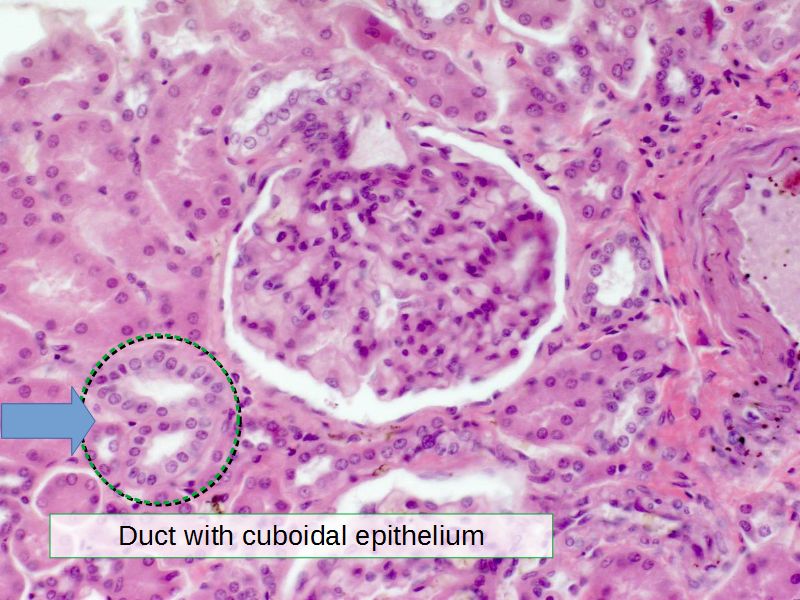

With which organ would you commonly associate cuboidal epithelium?Kidney

Renal corpuscle

- Tuft of capillaries

- grow into

- Blind end of nephron

- Several layers of epithelium

- Two sides

- Vascular pole

- Tubular pole